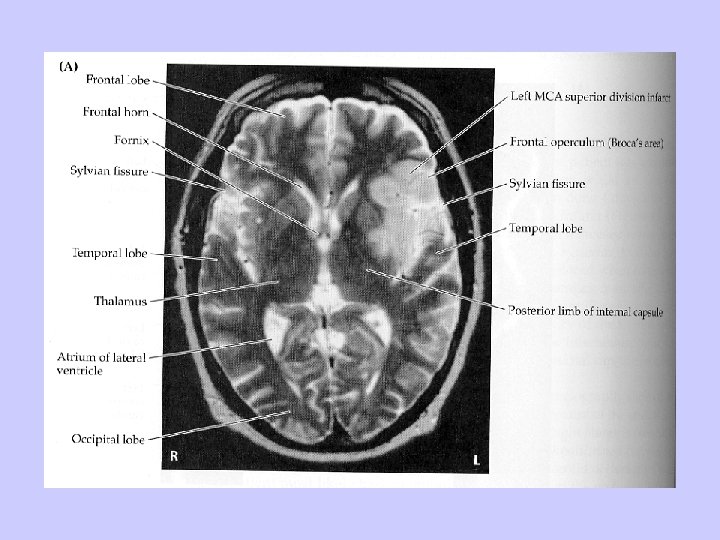

Middle Cerebral Artery Syndrome This is the most frequently encountered stroke syndrome. The clinical picture varies according to the site of occlusion of the vessel and to the availability of collateral circulation. The conglomerate clinical signs and symptoms of this syndrome consist of: 1. Contralateral hemiplegia or hemiparesis (complete or partial paralysis) affecting primarily the face and upper extremity and, to a lesser degree, the lower extremity. Weakness is greatest in the contralateral hand because more proximal limb and trunk muscles as well as facial muscles have greater representation in both hemispheres. 2. Contralateral sensory deficit, also more prominent in the face and upper extremity than in the lower extremity. Position, vibration, deep touch, two-point discrimination, and stereognosis are more affected than pain and temperature because the latter two sensory modalities may be perceived at the thalamic level. 3. Contralateral visual field deficit because of damage to the optic radiation, the tract that connects the lateral geniculate nucleus with the visual cortex. Depending on where the lesion in the optic tract is located, the visual field deficit may be a homonymous hemianopia (half-field deficit) or a quadrantanopia (quadrant-field deficit). 4. Contralateral conjugate gaze paralysis because of the involvement of the frontal eye field (area 8 of Brodmann). The gaze paralysis is usually transient for 1 to 2 days. The reason for this transient duration is not clear.

Middle Cerebral Artery Syndrome (con’t) 5. Aphasia (with impairment of repetition) if the dominant (left) hemisphere is involved. The aphasia may be of Broca’s, Wernicke’s, or global variety depending on the involved cortical region. 6. Inattention and neglect of the contralateral half of body or space and denial of illness if the nondominant (right) hemisphere is involved. 7. Spatial perception disorders if the right, nondominant hemisphere is involved. This includes such difficulties as copying simple pictures or diagrams (constructional apraxia), interpreting maps or finding one’s way out (topographagnosia), and putting on clothes properly (dressing apraxia). 8. Gerstmann syndrome (finger agnosia, acalculia, right-left disorientation, and pure dysgraphia).

Cortical infarct involving the ventral (arm & head regions) of the precentral gyrus and Broca’s speech area (MCA)